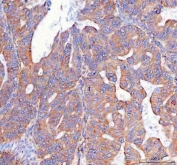

IHC staining of FFPE human ovarian cancer tissue with Prostaglandin E synthase 2 antibody. HIER: boil tissue sections in pH8 EDTA for 20 min and allow to cool before testing.